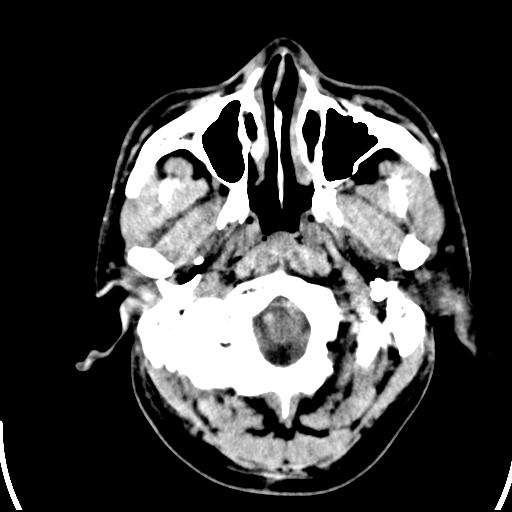

标题: CT25435:头皮下高密度影???

头皮下高密度结节影???临床上在老年男性比较常见。大家看看是什么?成因是? 本例患者,男性,51岁。外伤来诊。无染发史及发根植入史。

考虑异物。

皮下钙化点

没见过,可能为毛囊钙化。

这种东西有时要结合触诊和望诊。